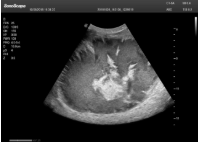

肝癌